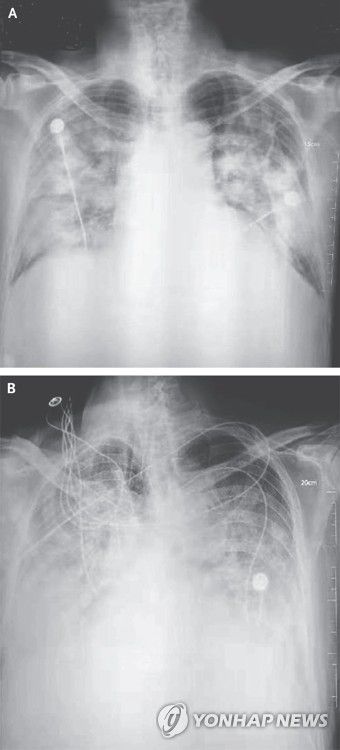

우한 폐렴 환자의 흉부 방사선 사진 |

AI가 검출할 수 있는 이상 소견은 ▲ 결절(폐에 생긴 작은 혹) ▲ 경화(폐 조직 일부가 딱딱하게 굳는 현상) ▲ 간질성 음영(폐 조직 사이의 공간에 이상이 생겨 X선 영상에서 비정상적으로 보이는 부분) ▲ 흉막삼출(폐를 둘러싼 막 사이 공간에 물이 차는 현상) ▲ 기흉(폐에 구멍이 생겨 공기가 새어 나오는 상태) 등 5가지 주요 질환이다.